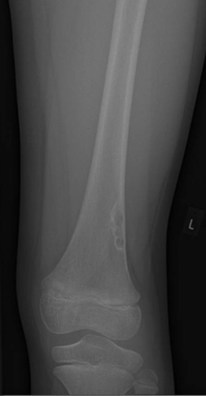

The radiograph below shows a malignant bone tumour in the distal femur (note the soft tissue swelling and irregular cortex)